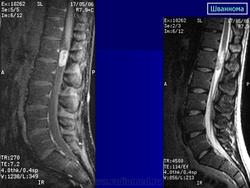

ГМ. СМ. Шванномы. +

Шванномы.